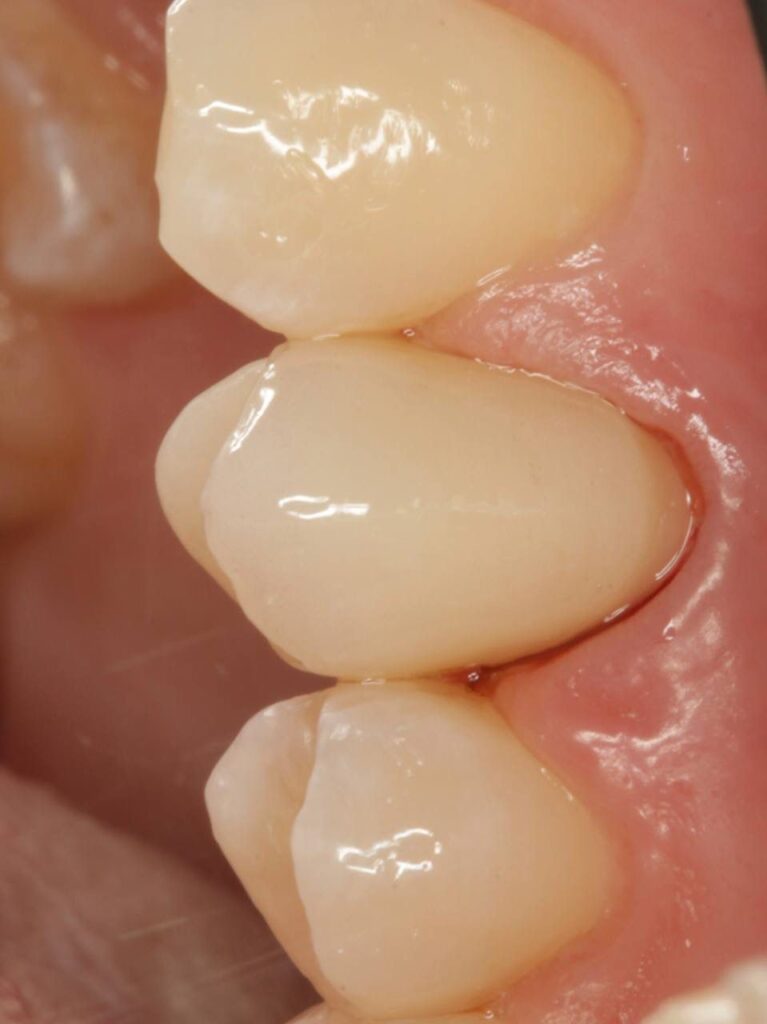

Специализация: терапия(эндодонтия), ортопедия, имплантология.